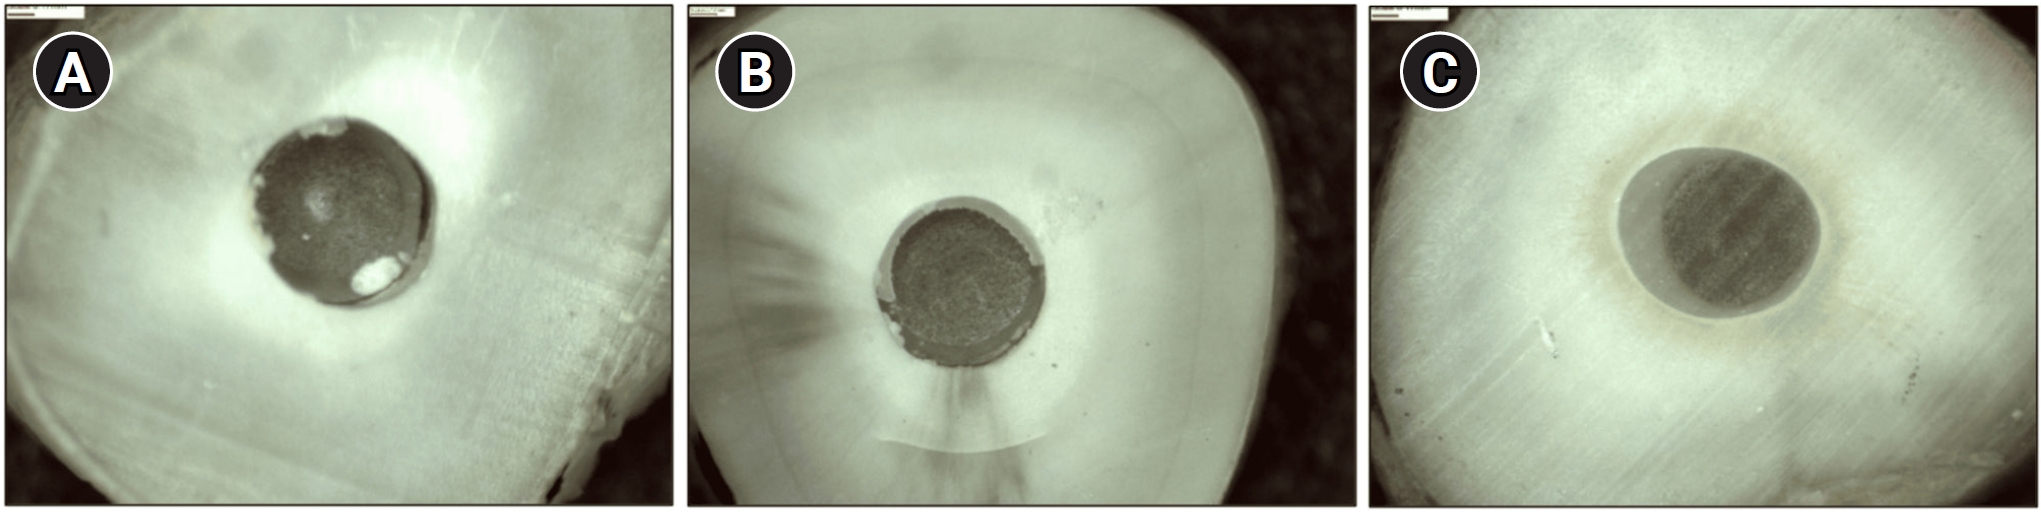

The roots were embedded in chemically cured acrylic resin blocks and transversely sectioned using a diamond disc under continuous water cooling with a precision cutting machine (Isomet 1000; Buehler, Lake Forest, IL, USA). Each specimen was sectioned into three slices, measuring 2 ± 0.3 mm in thickness, corresponding to the cervical, middle, and apical thirds of the post space. Each group produced 30 slices, with 10 from each third (n = 10), totaling 120 slices. No specimens were lost during sectioning. To avoid any compromise to the cement interface, push-out tests were performed immediately after sectioning (Figure 1).

Each slice was examined under a stereomicroscope (StereoDiscovery V20; Carl Zeiss, Göttingen, Germany) at 10× magnification by two operators. In cases where discrepancies arose, a third operator provided the final assessment. Failure patterns were categorized as follows: adhesive at the cement/dentin interface, adhesive at the cement/post interface, cohesive in the dentin, cohesive in the cement, cohesive in the post, and mixed. Mixed failures included cohesive failure in the cement combined with adhesive failure at the post-cement interface, cohesive failure in the cement with adhesive failure at the cement-dentin interface, or a combination of adhesive failures at both interfaces with cohesive failure in the cement (Figure 2).

Figure 2.

Failures observed in the present study. (A) Adhesive failure at the cement-dentin interface. (B) Mixed failure: adhesive at the post-cement interface, adhesive at the cement-dentin interface, and cohesive in cement. (C) Adhesive failure at the cement-post interface.

rde-2025-50-e29f2.jpg